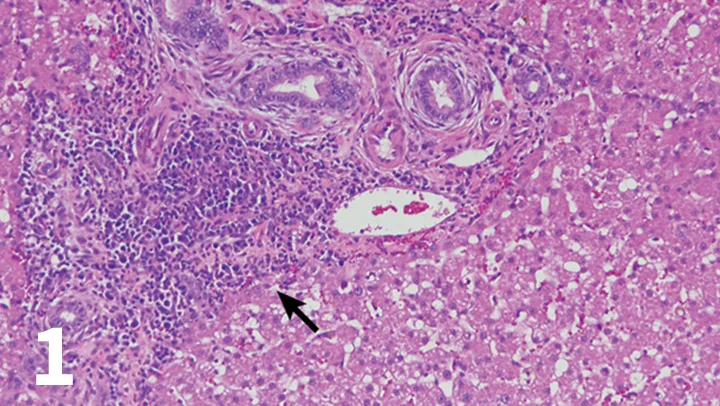

Figure 1

H&E-stained section (20× objective ) of a feline liver with periductal lymphocytic inflammation (arrow) centered around portal areas with concentric rings of fibrosis consistent with lymphocytic cholangitis.

The chronicity of lymphocytic cholangitis is believed to represent a later stage of neutrophilic cholangitis or may represent a separate disease entity. It is characterized by a moderate-to-marked infiltration of the portal areas by small lymphocytes with or without biliary hyperplasia, portal or periductal fibrosis, or bridging fibrosis (Figure 1). The underlying cause is unknown, but 1 possible cause is an immune disorder.<sup11 sup>